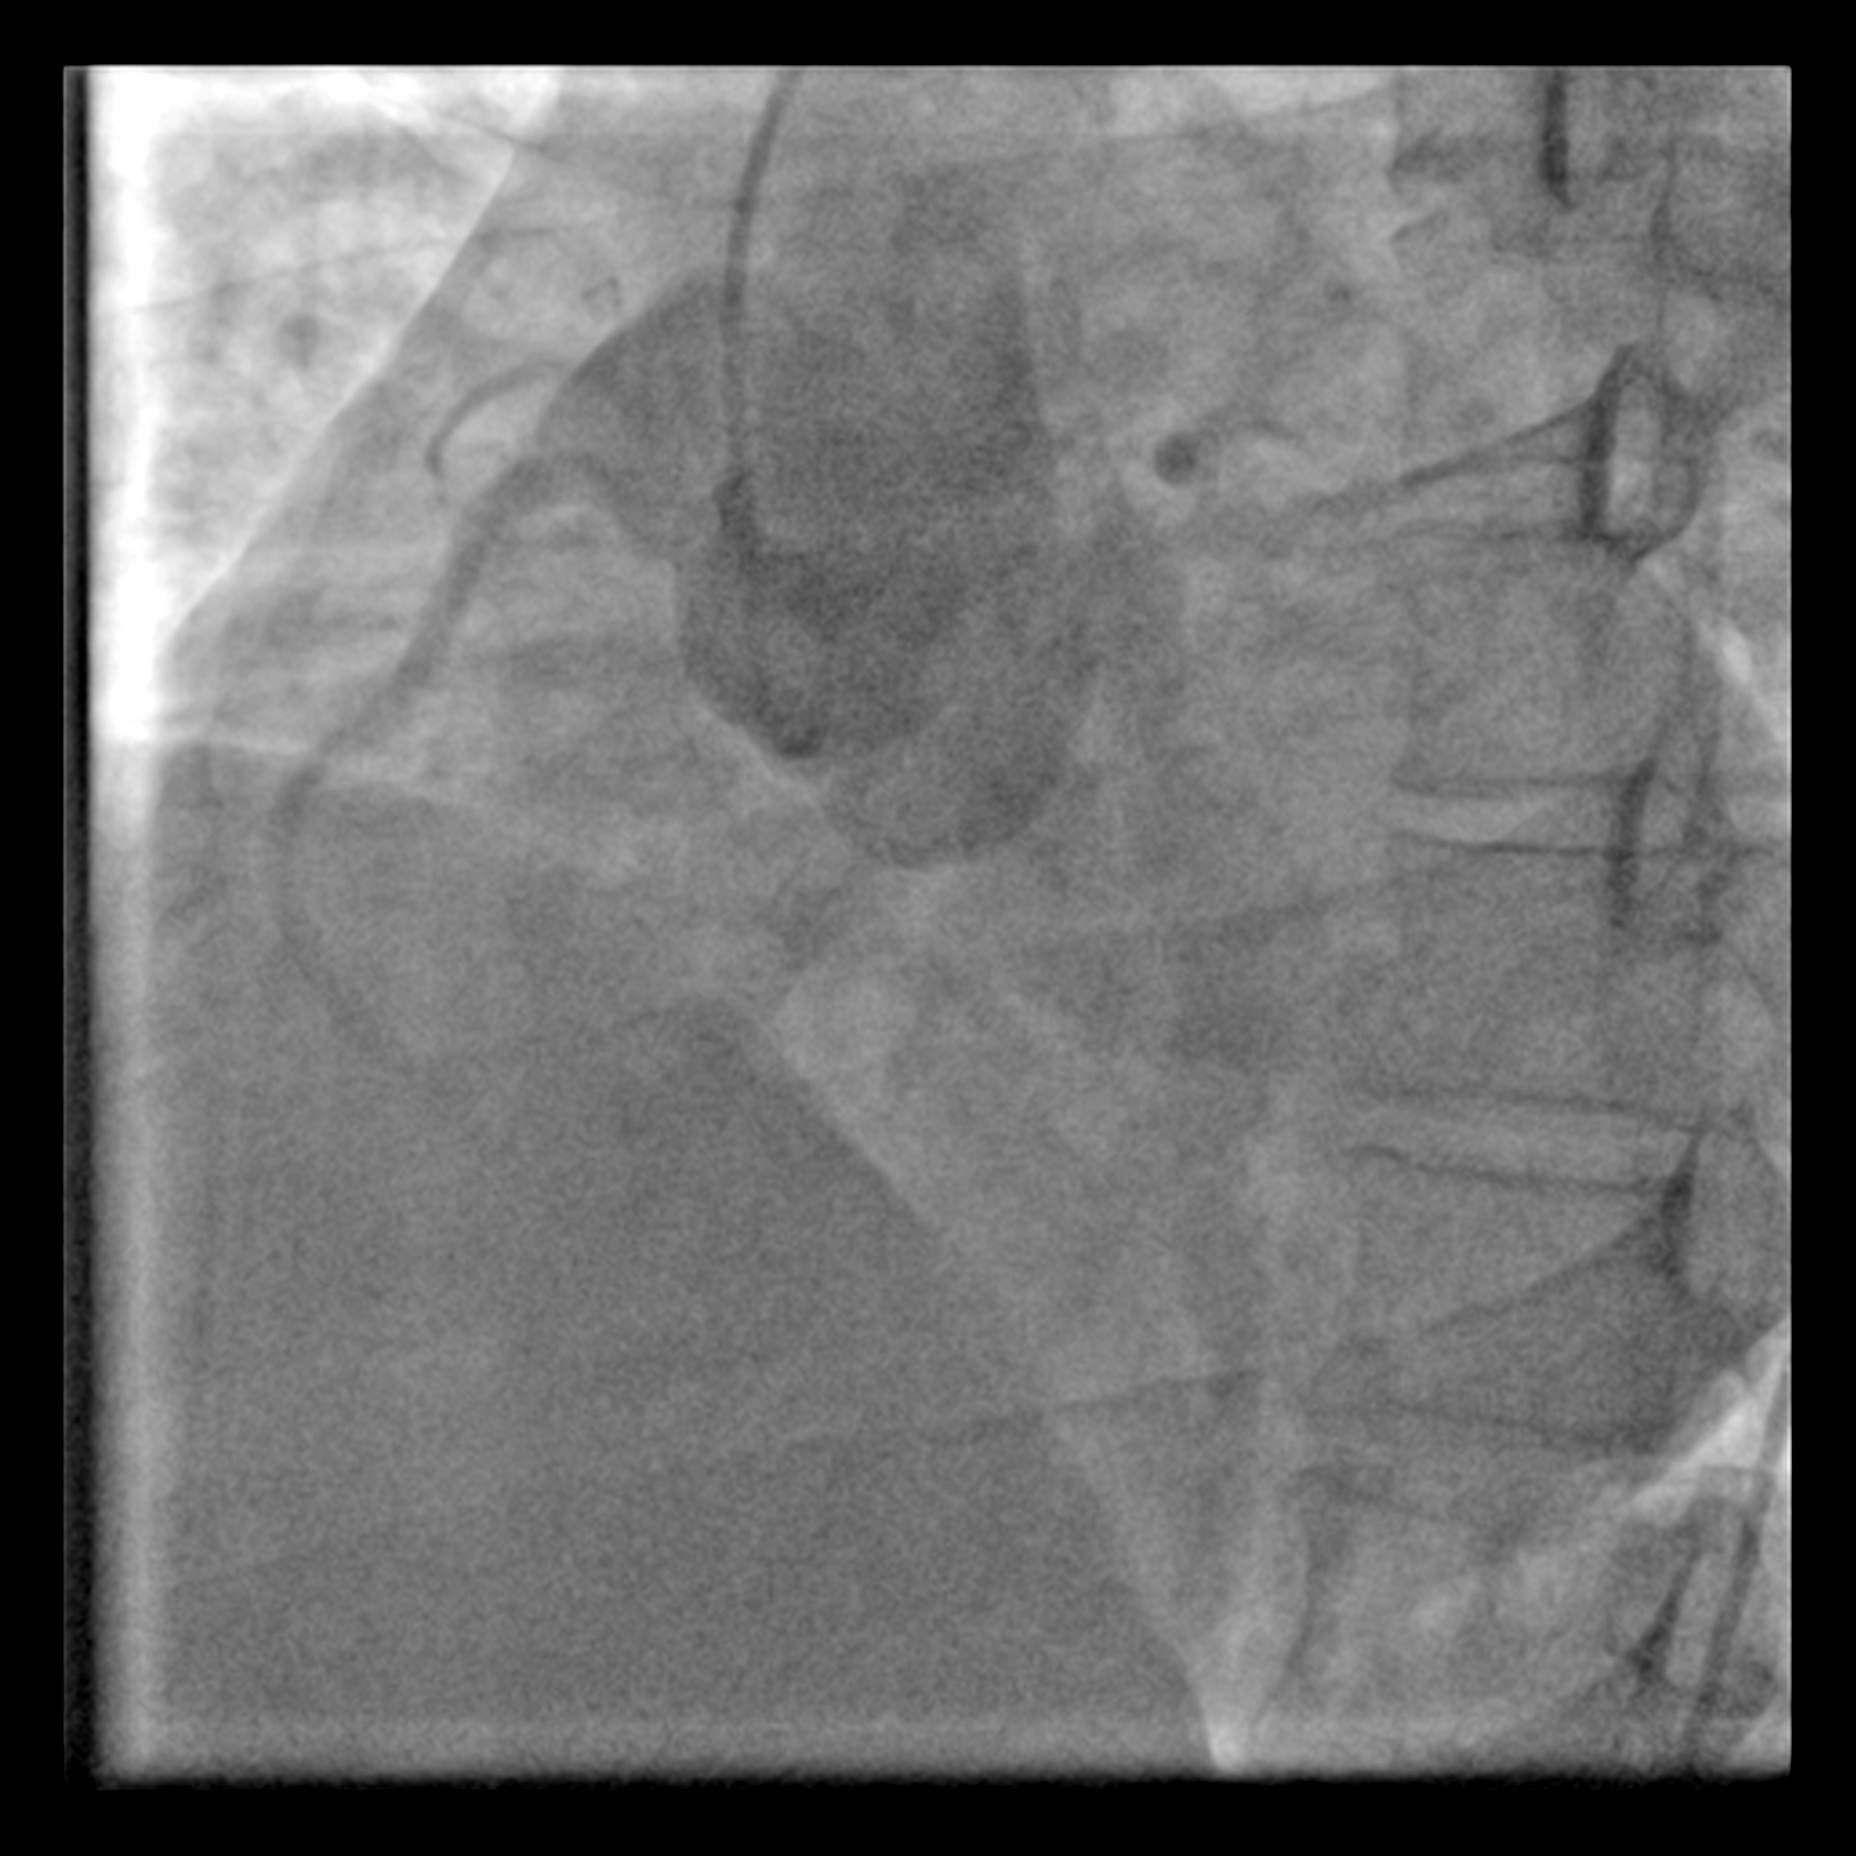

Via right femoral arterial access, a pigtail catheter was placed in SOV & non selective shot was taken with injector 2 views were used: left anterior and right anterior oblique view were taken to delineate the shunt. Right heart catheterisation was not perform in view of absence of pulmonary hypertension albeit left ventricle is dilated from echocardiography.